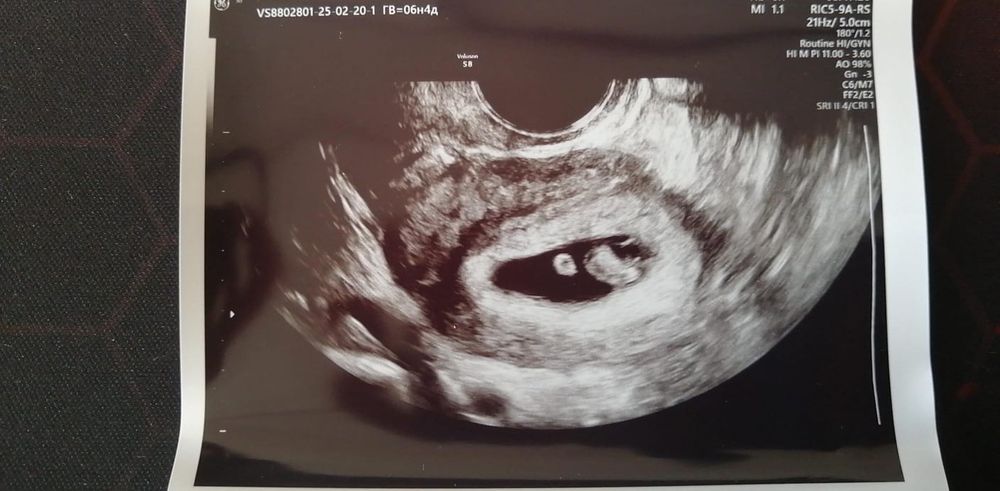

Первое узи на 6н4д.

Маточная, сроку соответствует, сердечко тук-тукает) Показали эмбриончик, дали послушать сердце. Ощущения конечно непередаваемые, неужели я вправду беременна!)